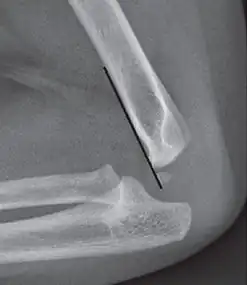

The anterior humeral line is not reliable in children with sparse ossification of the capitulum, such as in this 6 months old child.[9]